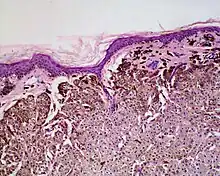

Balloon cell nevus is a benign nevus.[1] It appears like a melanocytic nevus.[2]

Histologically it is characterized by swollen, pale, polyhedral melanocytes, with pale cytoplasm and a central nucleus.[2] It is different to balloon cell melanoma,[3] which has larger nuclei and is structured like a melanoma.[1]